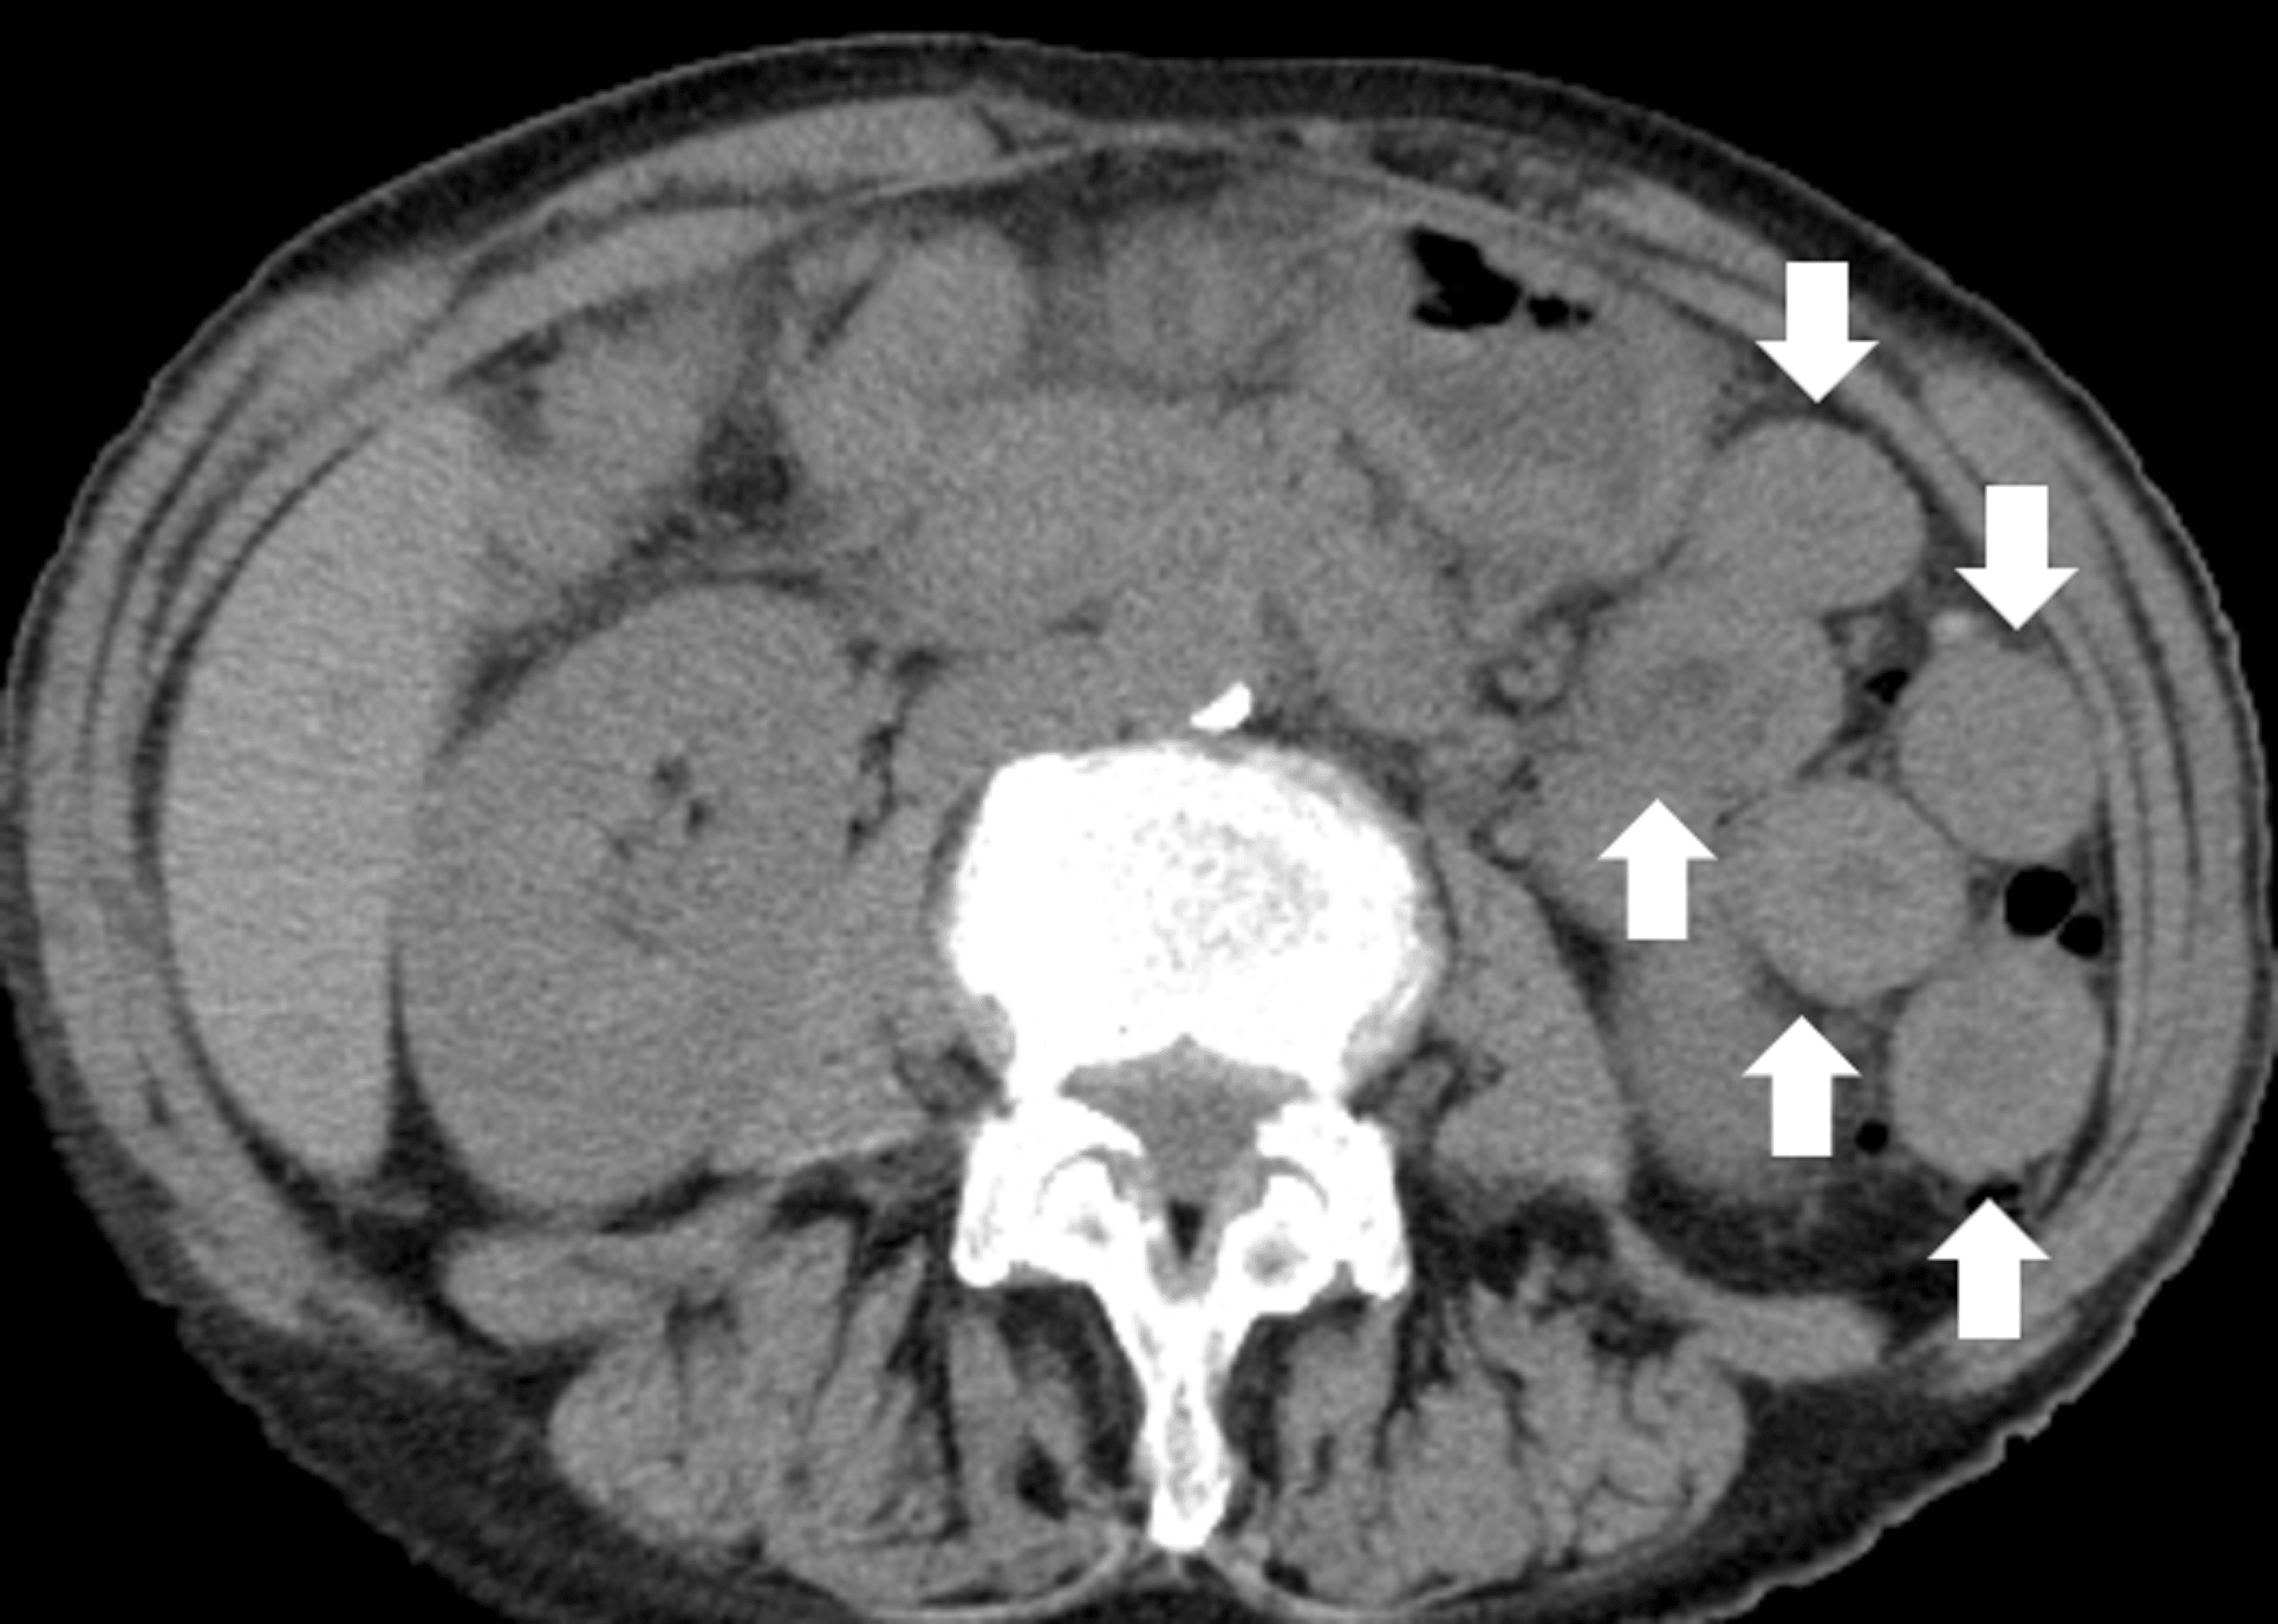

Eosinophilic esophagitis An increasingly recognized cause of dysphagia